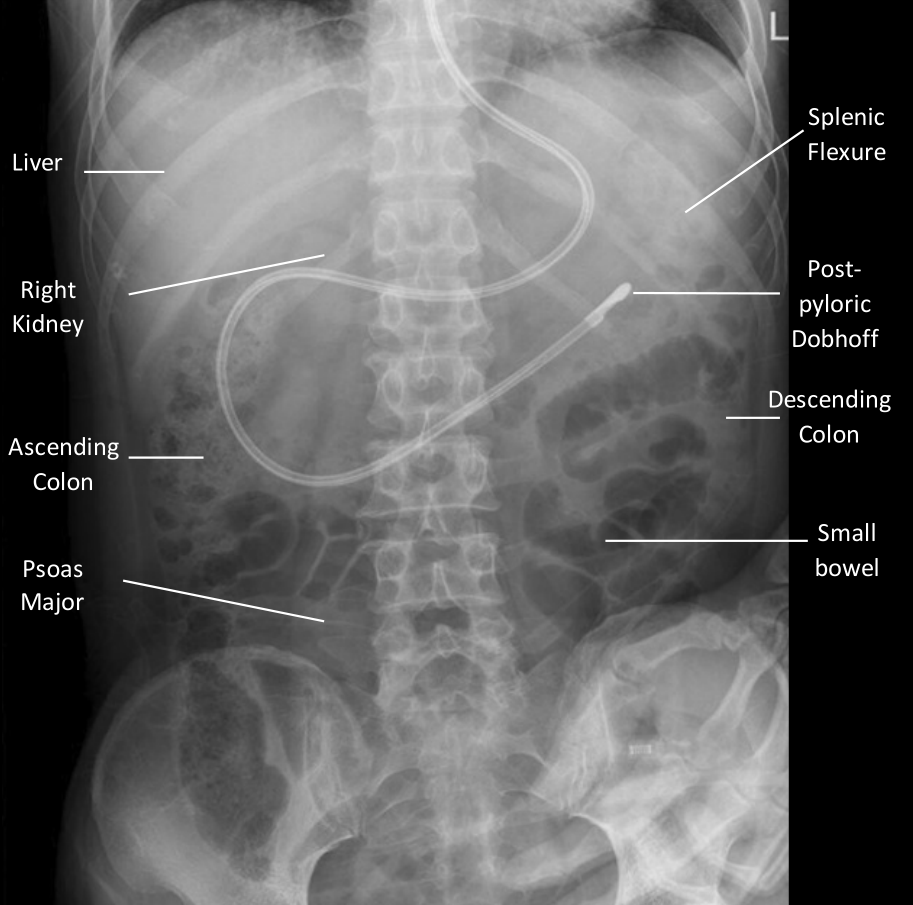

Basic Abdominal X ray Interpretation Internal Medicine Residency Handbook